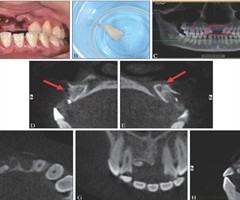

上颌中切牙完全脱位后异位牙再植及延期种植修复1例

[中图分类号] R781 [文献标志码] B [doi] 10.7518/hxkq.2025.2024395 [摘要]牙外伤是口腔临床工作中较为常见的急症之一,发病率高,上颌中切牙最易受累。本文报告1例17岁女性患者,因外伤导致11、21牙...